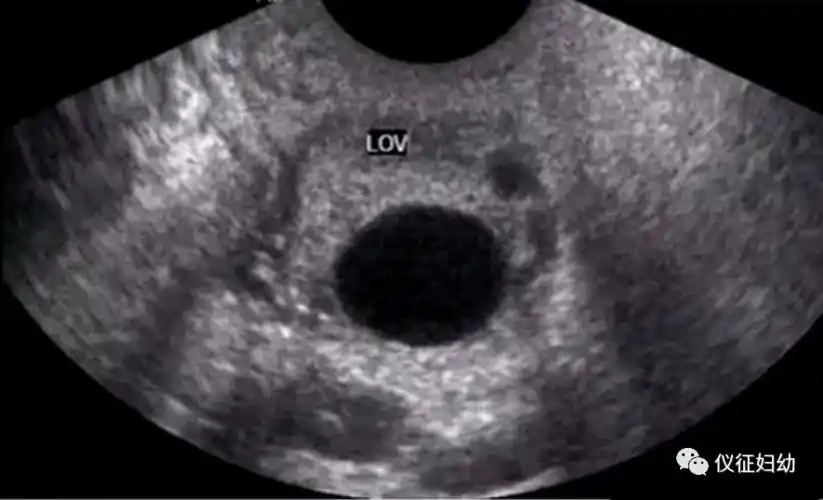

科普经阴道b超监测排卵不可不知的细节